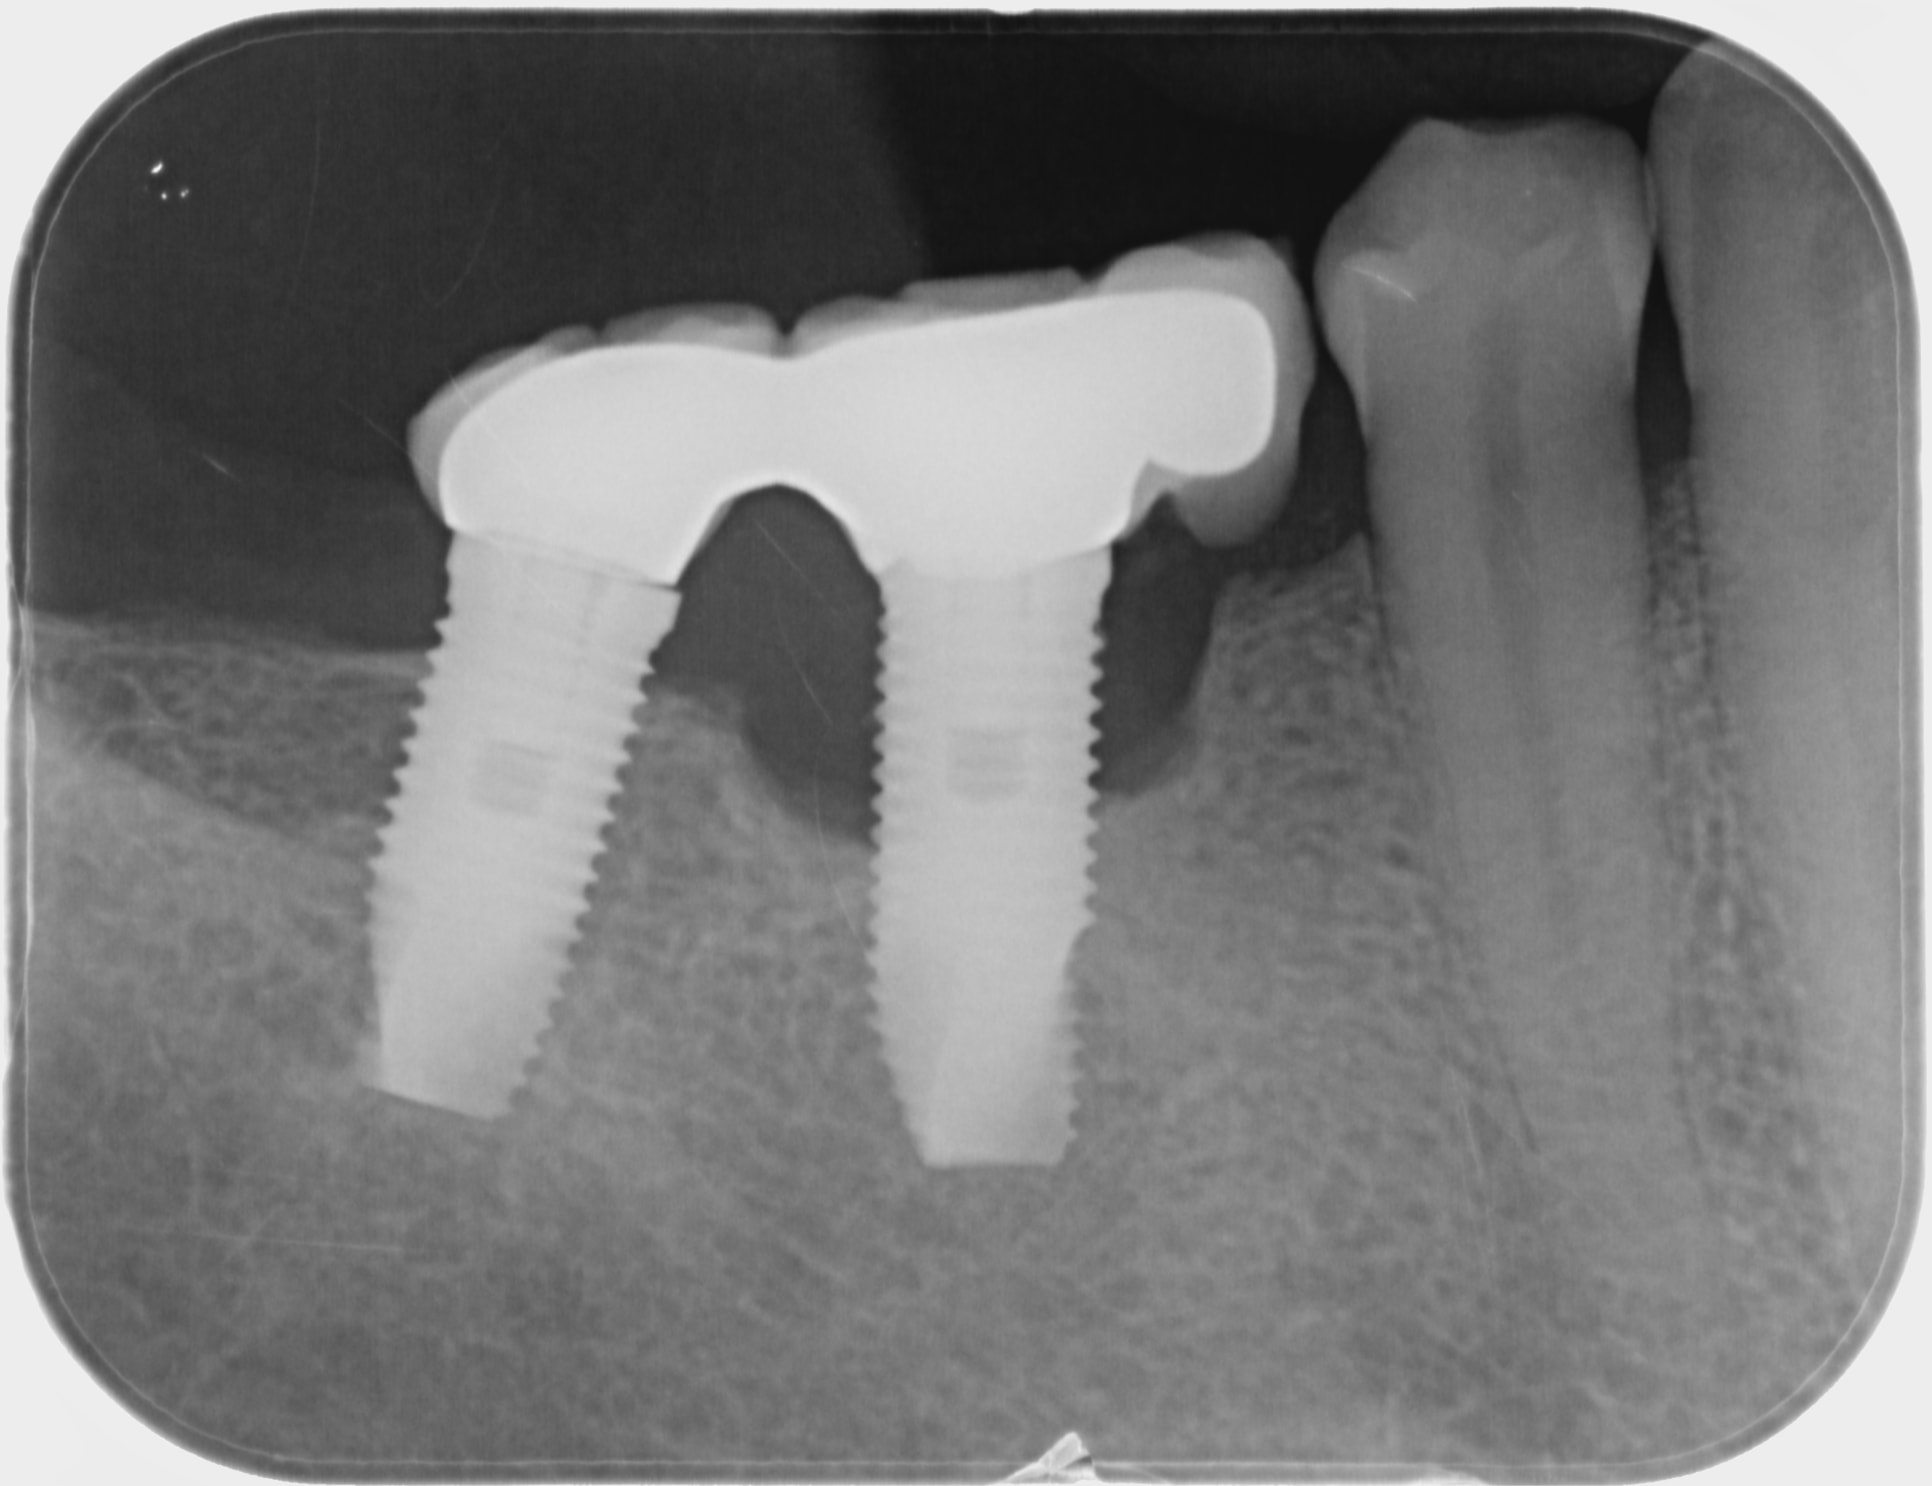

comment gérez vous ce cas de cratérisation?

Patient 63 ans bonne santé. Implant posé en 2003,

poche périphérique de 5 à 6 mm, beaucoup de tissu de granulation et suppuration.

la cause n'en est-elle pas la surcharge du pilier, surcharge causée par l'extension mésiale en porte à faux ?